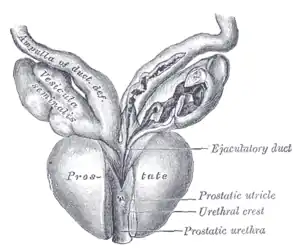

| Vesiculæ seminales and ampullæ of ductus deferentes, seen from the front. Posterior urethral valves are at the dorsal aspect (back) of the prostatic urethra. | |

Posterior urethral obstruction was first classified by H. H. Young in 1919. The verumontanum, or mountain ridge, is a distinctive landmark in the prostatic urethra, important in the systemic division of posterior valve disorders: